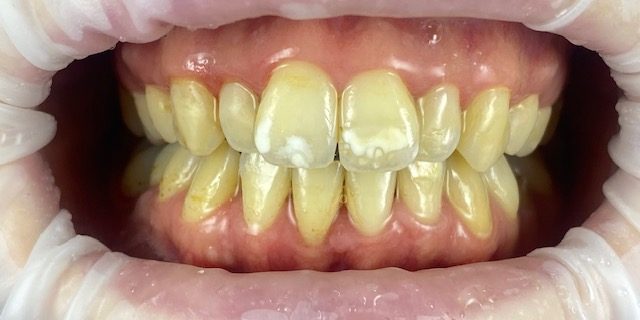

Las lesiones de mancha blanca son alteraciones de la superficie del esmalte, y constituyen una de las alteraciones que con más frecuencia producen una afectación estética de los dientes.

Una alternativa mínimamente invasiva para el tratamiento estético de estas lesiones es la infiltración de resina ICON , que presenta un índice de refracción similar al del esmalte sano y puede asimismo igualar la diferencia de la refracción de la luz.

El procedimiento es indoloro, no se daña el diente y conseguimos un resultado espectacular, como en este caso de la Doctora Granado.

INICIO

FINAL